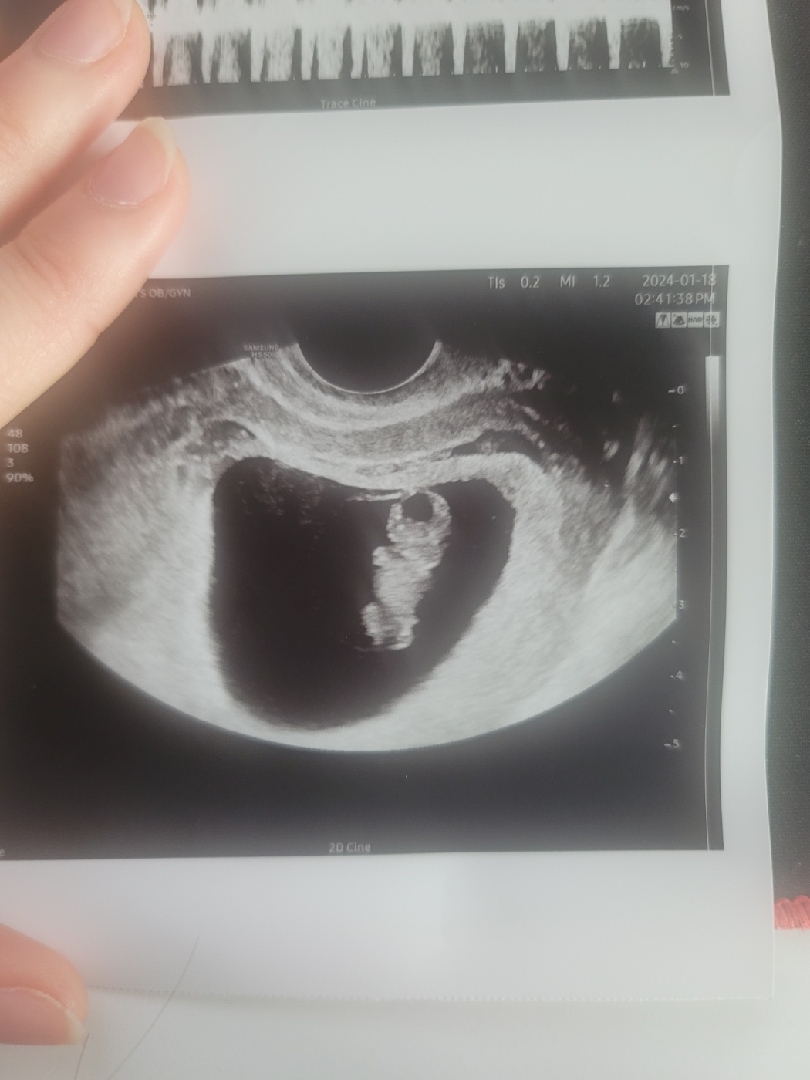

9주차 초음파 받았는데 다들 아들이라고 해서 궁금한데 같이 봐주실수있나요?

9주1일 되자마자 정기검사 받으러가서 초음파찍고 나왔는데 이미 육아중이신 어머님들이 사진을 보더니 9주차에도 보인다고 가운데에 달려있지 않냐고 하시는데 전 도통... 봐도 모르겠거든요..👉👈 9주차때 벌써 꼬식이가 달려있나요?

녜? ㅋㅋㅋㅋㅋㅋ 아뇨 ㅋㅋㅋㅋㅋㅋ 아들 딸 모두 첨엔 돌출되어있어요! 그리고 9주차라면 저건 생식기가 아니고 꼬리일 확률이 더 높어요!! ㅋㅋㅋㅋ 아니 이미 출산하샸던 분들이 왜 ㅋㅋㅋㅋㅋㅋ그러시대용 😅😅